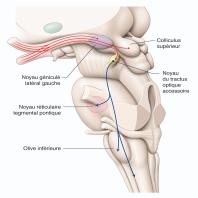

- eFig. 5-6 - Champ récepteur du canal parvocellulaire avec de gauche à droite : une CGR naine à centre rouge ON, à centre rouge OFF, à centre vert ON et à centre vert OFF

- eFig. 5-8 - Anatomie macroscopique de la voie rétinocolliculaire et du système optique accessoire en coupe axiale passant par les noyaux géniculés latéraux en vue de profil gauche